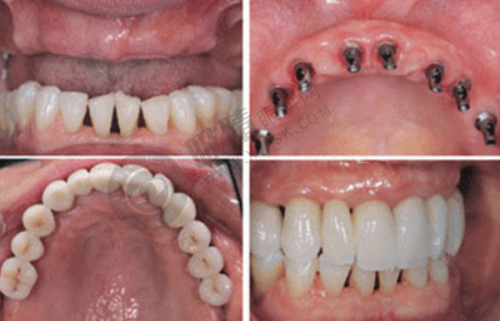

陕西省人民医院口腔科可开展全口数字化种植、ONLY 植骨术、骨劈开术、GBR 手术、即刻种植、上颌窦外提升等高难度的种植技术。

西安交通大学医学校第一附属医院口腔科引入机器人种植(5 分钟/颗)、3D 导板设计,减少人力与耗材浪费;提供3D 数字化模拟矫正方案,提前预览牙齿移动轨迹。

西安交大口腔正畸科提供3D 数字化方案设计,修复科引进德国即刻种植技术